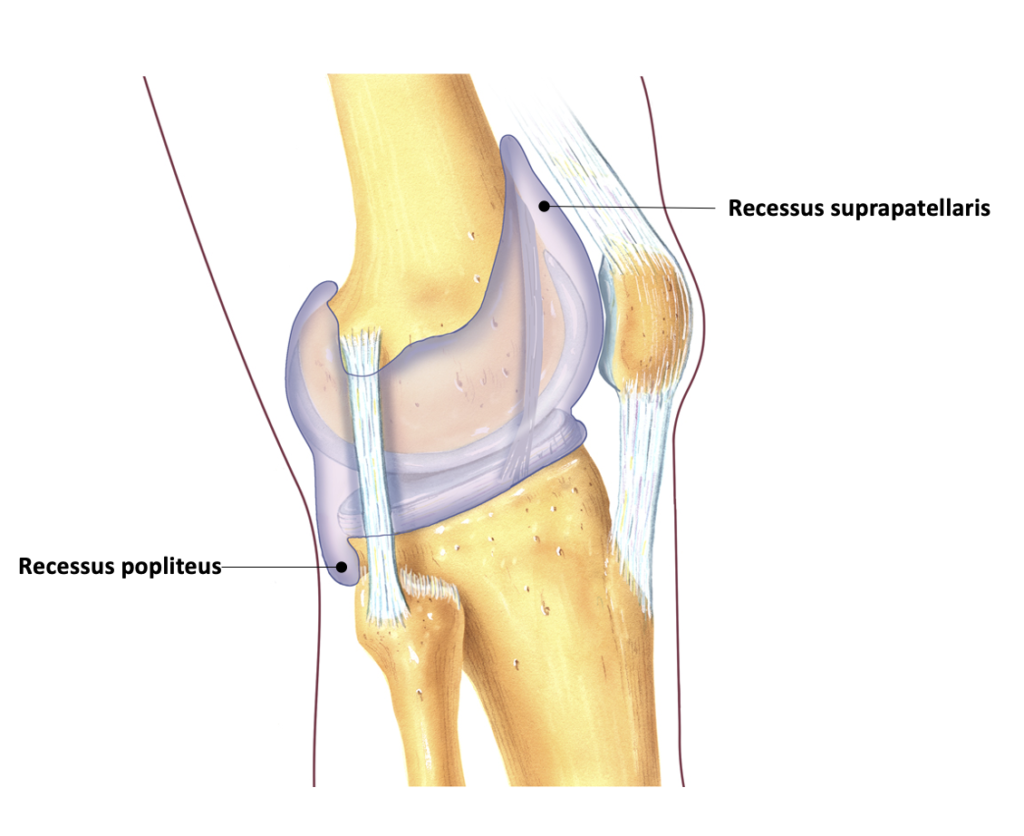

Kne, recessus suprapatellaris

Sjekk patella dip, positiv test dersom > 20ml som tyder på intraartikulær væske.

Patella dip test, positiv når > 20 mø intraartikulær væske

- Patella dip test → intraartikulær væske (positiv test når >20 ml intraartikulær væske)

Mange tilstander i kneleddet er utløst av traume. Det er derfor veldig viktig at man i anamnesen tar hensyn til gamle eventuelt nylig oppståtte traumer. I den eldre befolkningen er kneleddsartrose den vanligste tilstanden. Klinikken er sammensatt av smerter ved aktivitet og ofte leddhevelse. Ved klinisk undersøkelse foreligger det ofte et kapsulært bevegelsesmønster ved passive tester (mer redusert fleksjon enn ekstensjon). Hydrops testes med patella dip test.